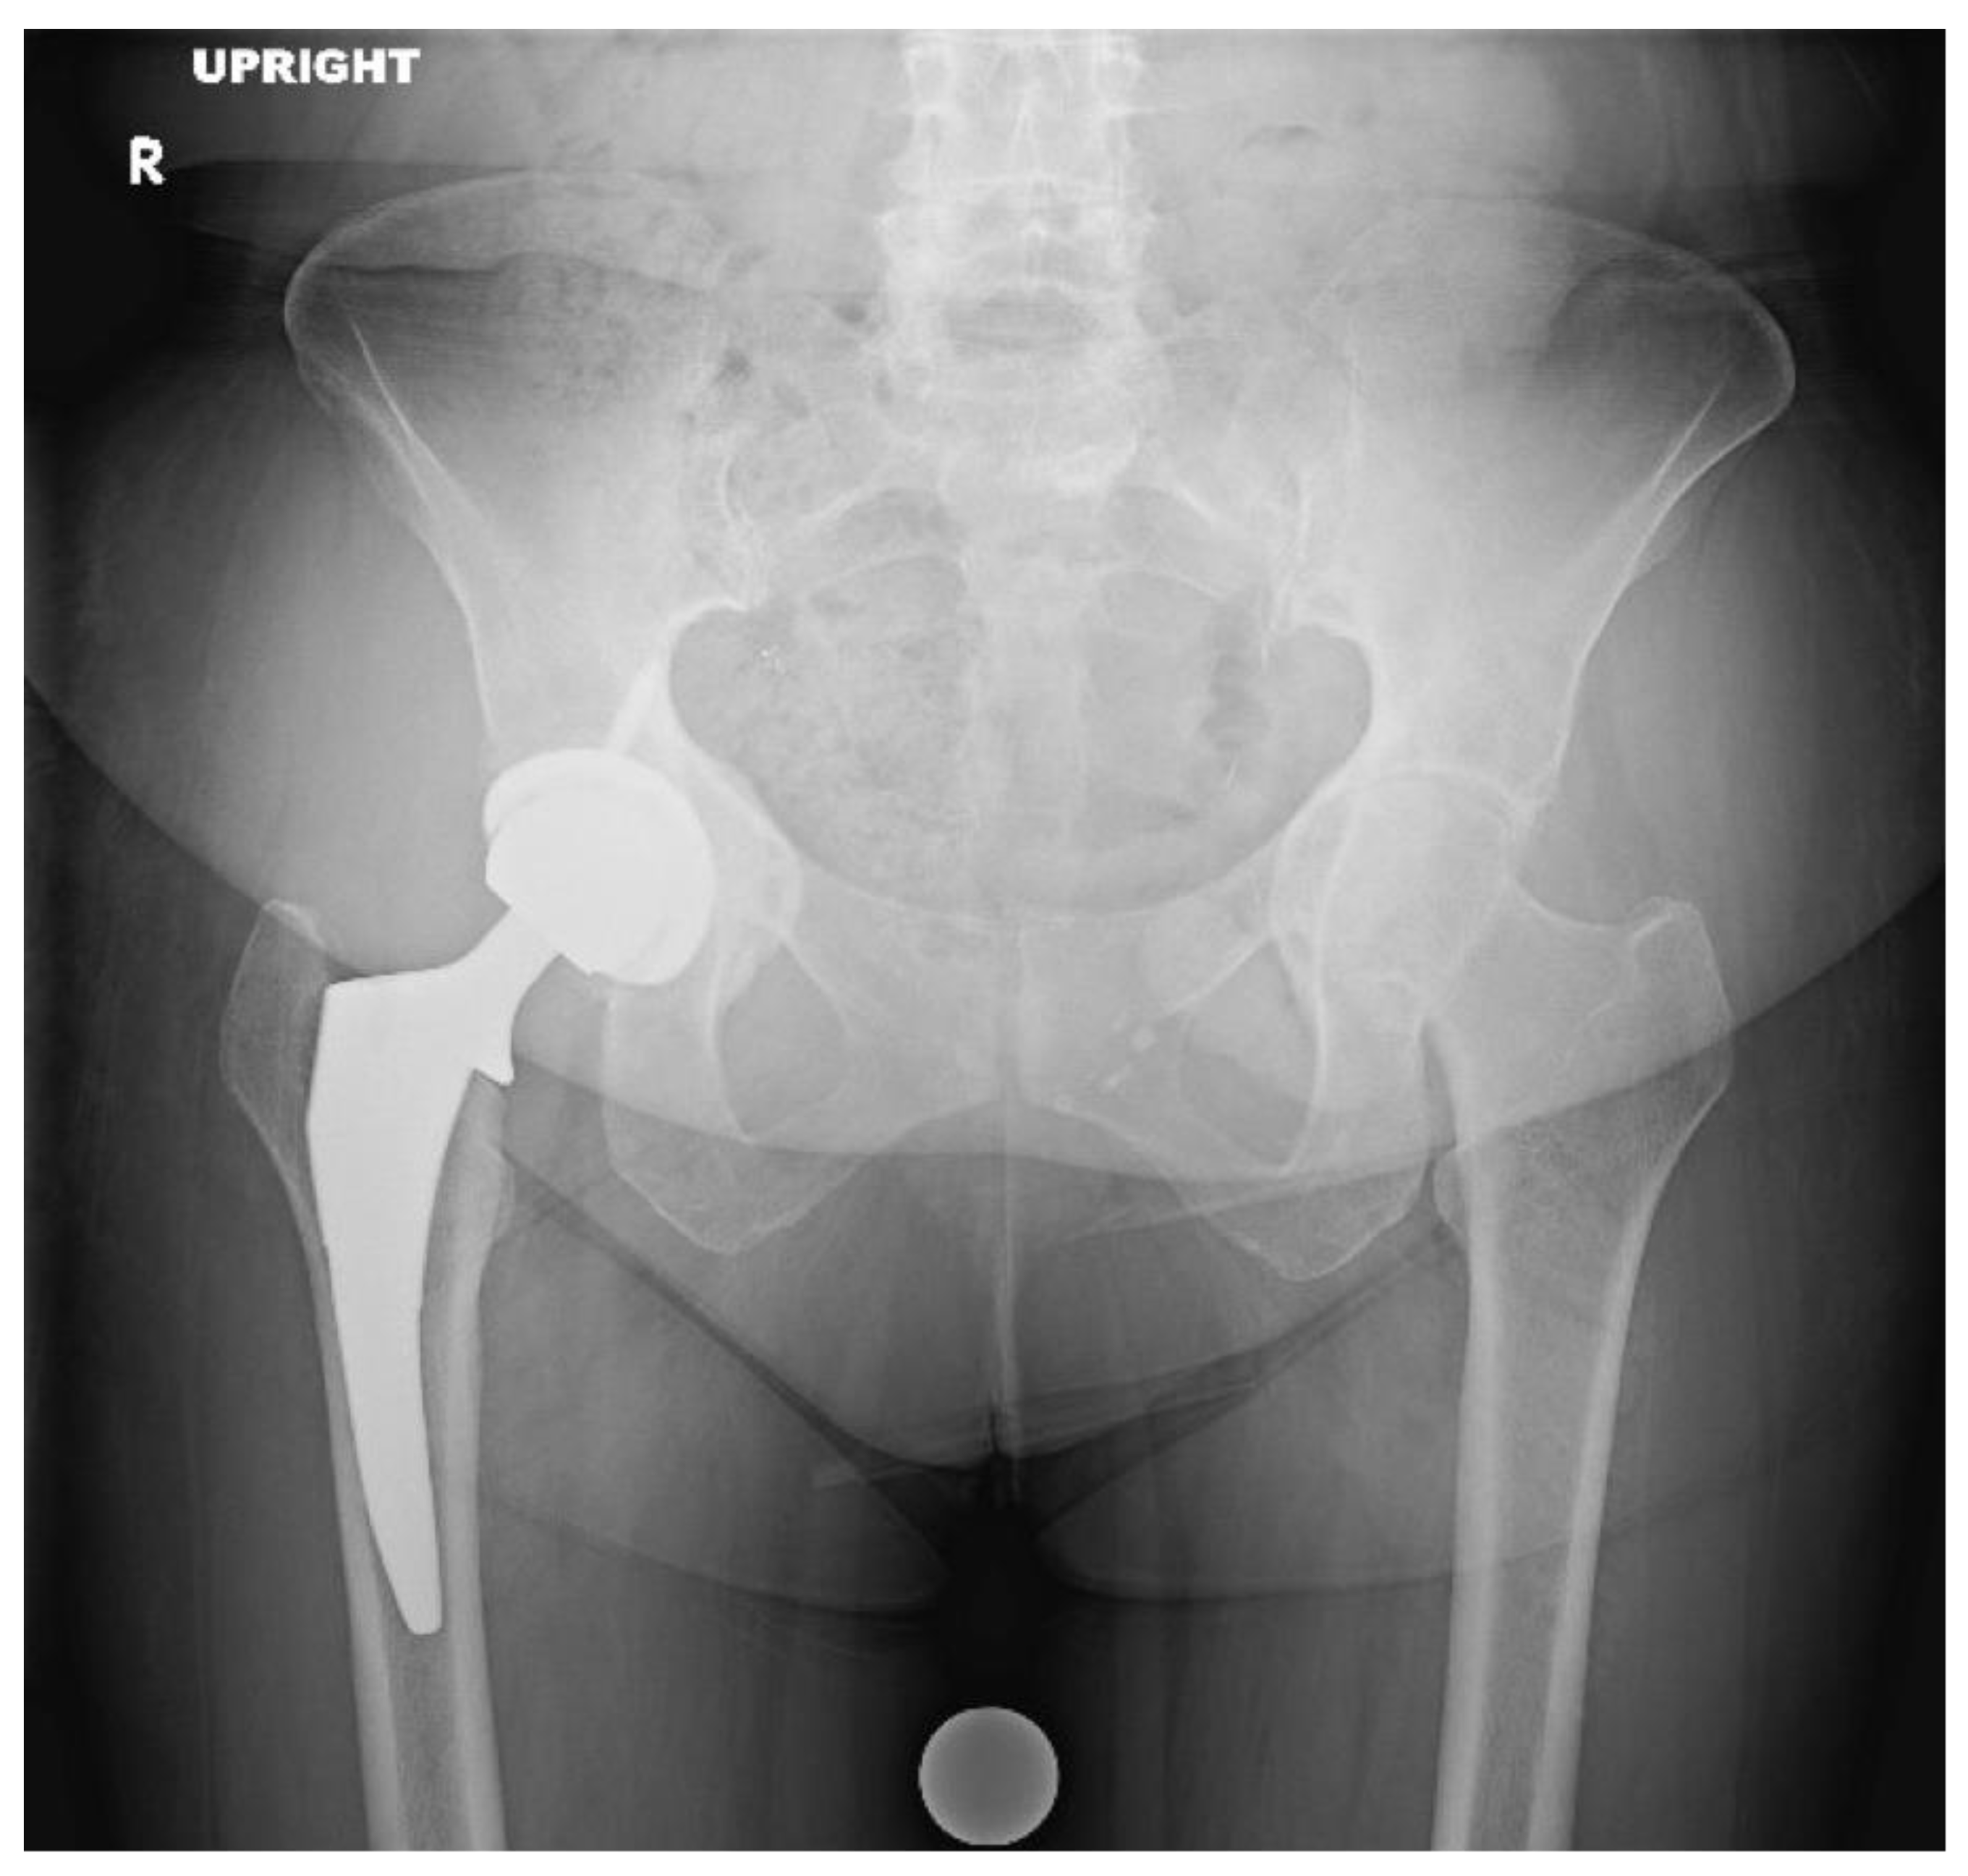

3.3. Protrusio Cases